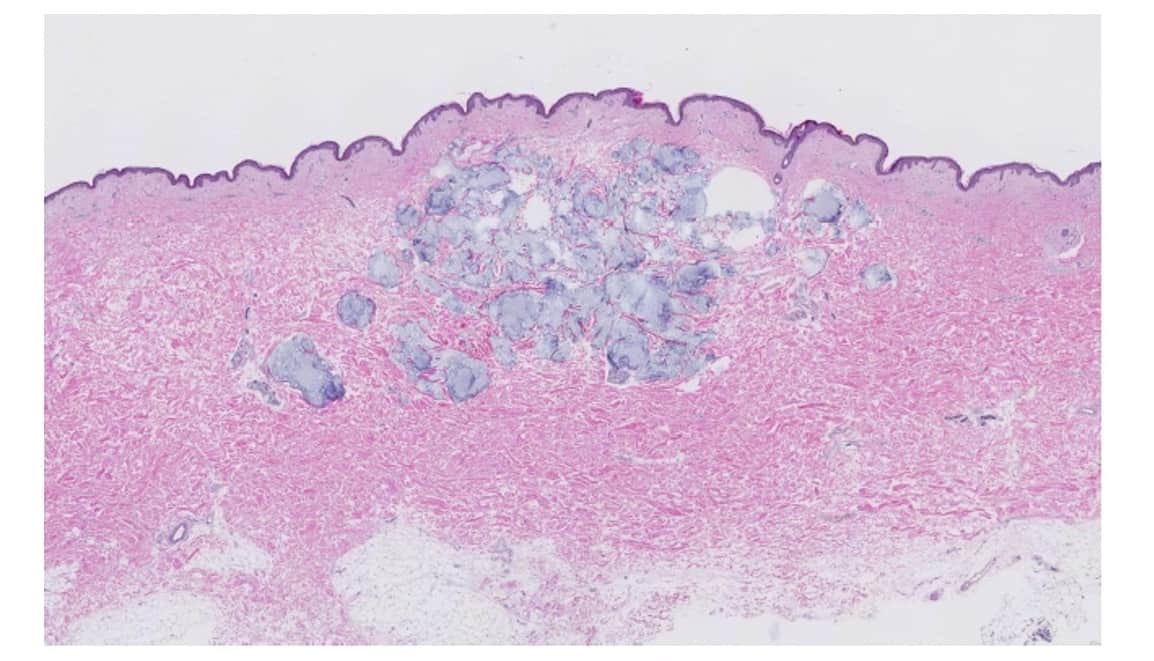

玻尿酸(HYALURONIC ACID 亦稱透明質酸)是人體肌膚內自然存在的一種成分,以膠狀型態存在於皮膚真皮層中的一種物質,具有很強的保濕儲水功能,它的透明質分子能攜帶500倍以上的水分,可以增加肌膚彈性、潤滑性及肌膚柔軟性、維持體內水分、保持結締組織的潤滑與構成組織黏液等等,是人體肌膚不可或缺的重要成分。

年輕的肌膚因為含有豐富的玻尿酸,因此觸感柔軟有彈性,使肌膚結構與外觀豐潤飽滿;隨著年齡增長,體內的玻尿酸逐漸流失,因此皮膚漸漸出現鬆垮、凹陷、皺摺等等老化現象。玻尿酸目前被廣泛運用在「保養品」及「醫療行為」上,因為玻尿酸具有保濕、填充皮膚體積,及好塑型的特點。

用於「醫療行為」上,玻尿酸會依照施打部位的不同,可以分為淺層施打跟深層施打,淺層施打就是施打於表皮跟真皮之間,深層的話就是施打於骨膜之上。